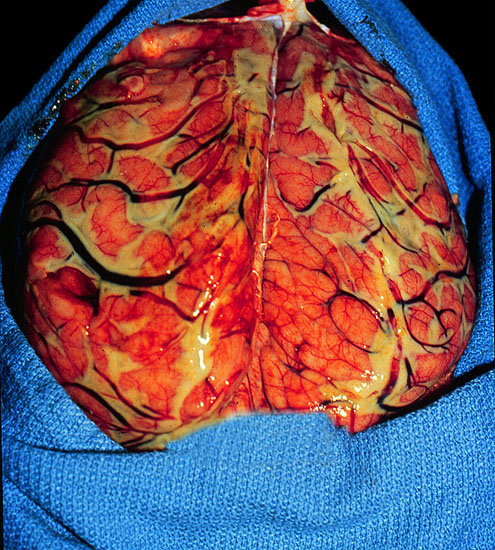

Purulent meningitis (H. influenzae), convexity.